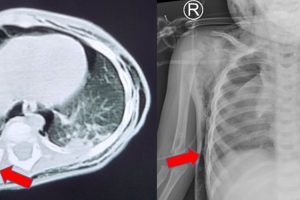

Trẻ chấn thương vỡ lách độ IV – Vừa qua, bệnh viện Nhi Đồng Thành Phố tiếp nhận một trẻ H. L. M. T. 5 tuổi, nữ, tạm trú tại quận Bình Tân. Khai thác bệnh...